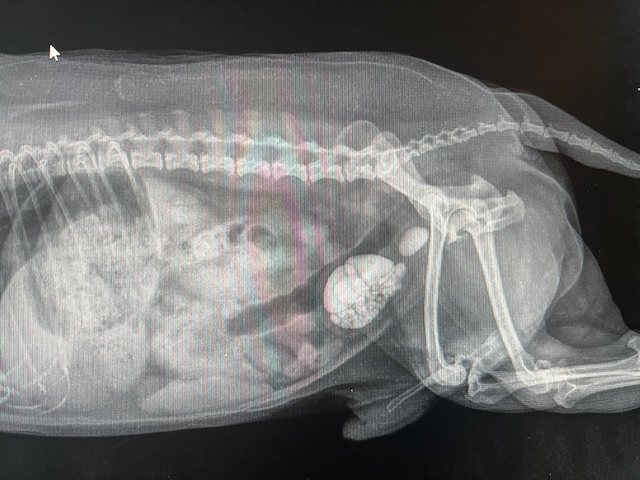

De blaas zat volledig gevuld met talrijke blaasstenen en bovendien zat er opnieuw een steentje vast in de urethra, waardoor de urine niet meer kon passeren. Ondanks de eerdere urethrostomie had een steen zich toch op een ongunstige plaats vastgezet, met opnieuw een levensbedreigende situatie tot gevolg.